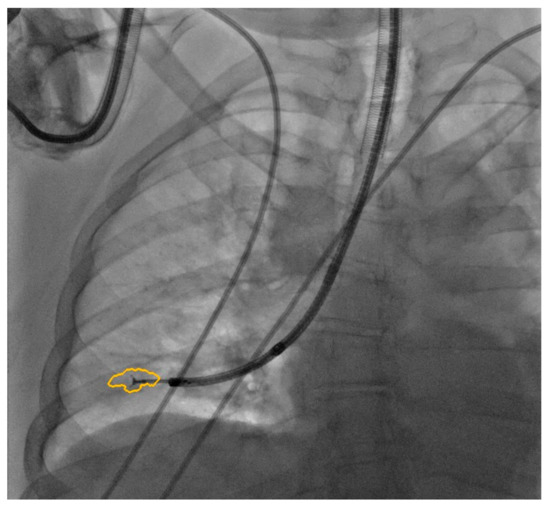

- Casal, R.F.; Sarkiss, M.; Jones, A.K.; Stewart, J.; Tam, A.; Grosu, H.B.; Ost, D.E.; Jimenez, C.A.; Eapen, G.A. Cone Beam Computed Tomography-Guided Thin/Ultrathin Bronchoscopy for Diagnosis of Peripheral Lung Nodules: A Prospective Pilot Study. J. Thorac. Dis. 2018, 10, 6950–6959. [Google Scholar] [CrossRef] [PubMed]

- Ali, E.A.A.; Takizawa, H.; Kawakita, N.; Sawada, T.; Tsuboi, M.; Toba, H.; Takashima, M.; Matsumoto, D.; Yoshida, M.; Kawakami, Y.; et al. Transbronchial Biopsy Using an Ultrathin Bronchoscope Guided by Cone-Beam Computed Tomography and Virtual Bronchoscopic Navigation in the Diagnosis of Pulmonary Nodules. Respiration 2019, 98, 321–328. [Google Scholar] [CrossRef]